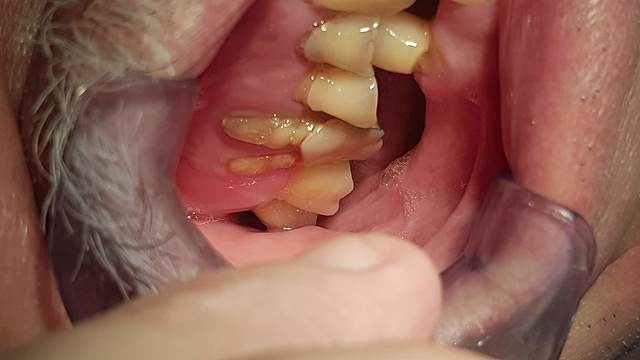

• Análisis radiográfico, Modelos de estudio y análisis intraorales.

Análisis radiográfico, Modelos de estudio y análisis intraorales.

Se realizó la elaboración de los materiales de estudio para poder crear un diagnostico adecuado sobre el tratamiento a realizar.

Disminución de la dimensión vertical.

Recesión gingival y perdida de cortical vertical por extrusión: 1.6

Ausencia: 2.6, 2.7, 3.5, 3.6, 3.7, 3.8, 4.4, 4.6, 4.7 y 4.8.

Caries: 2.8, 2.5, 2.4, 1.5 y 1.8

D. pulpar (1.4): necrosis pulpar.

D. periapical: periodontitis apical crónica.

D. pulpar (1.2, 2.1, 2.2, 2.3): pulpa sana, endodoncia por fines protésicos.

D. periapical: periápice sano.

F. desgaste: 1.3, 1.2, 1.1, 2.1, 2.2, 2.3, 2.4, 3.3, 3.2, 3.1, 4.1, 4.2, 4.3 y 4.5.

Amalgama: 1.7 y 1.6.